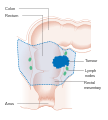

Staging

Staging is typically made according to the TNM staging system from the WHO organization, the UICC and the AJCC. The Astler-Coller classification (1954) and the Dukes classification (1932) are now less used.

The T stages of bowel cancer.

The T stages of bowel cancer. Dukes stage A bowel cancer; the cancer is only in the inner lining of the bowel.

Dukes stage A bowel cancer; the cancer is only in the inner lining of the bowel. Dukes stage B bowel cancer; the cancer has invaded the muscle.

Dukes stage B bowel cancer; the cancer has invaded the muscle. Dukes stage C bowel cancer; the cancer has invaded the nearby lymph nodes.

Dukes stage C bowel cancer; the cancer has invaded the nearby lymph nodes. Dukes stage D bowel cancer; the cancer has metastasized.

Dukes stage D bowel cancer; the cancer has metastasized.

Survival is directly related to detection and the type of cancer involved, but overall is poor for symptomatic cancers, as they are typically quite advanced. Survival rates for early stage detection is about five times that of late stage cancers. People with a tumor that has not breached the muscularis mucosa (TNM stage Tis, N0, M0) have a five-year survival rate of 100%, while those with invasive cancer of T1 (within the submucosal layer) or T2 (within the muscular layer) have an average five-year survival rate of approximately 90%. Those with a more invasive tumor yet without node involvement (T3-4, N0, M0) have an average five-year survival rate of approximately 70%. Patients with positive regional lymph nodes (any T, N1-3, M0) have an average five-year survival rate of approximately 40%, while those with distant metastases (any T, any N, M1) have an average five-year survival rate of approximately 5%.[105]